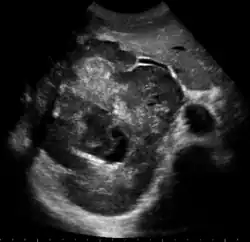

Upon discovery of a liver tumor, the main issue in the workup is to determine whether the tumor is benign or malignant. Many imaging modalities are used to aid in the diagnosis of malignant liver tumors. These include sonography (ultrasound), computed tomography (CT) and magnetic resonance imaging (MRI).

Ultrasound

Ultrasonography of liver tumors involves two stages: detection and characterization. Tumor detection is based on the performance of the method and should include morphometric information (three axes dimensions, volume) and topographic information (number, location specifying liver segment and lobe/lobes). The specification of these data is important for staging liver tumors and prognosis. Tumor characterization is a complex process based on a sum of criteria leading towards tumor nature definition. Often, other diagnostic procedures, especially interventional ones are no longer necessary. Tumor characterization using the ultrasound method will be based on the following elements: consistency (solid, liquid, mixed), echogenicity, structure appearance (homogeneous or heterogeneous), delineation from adjacent liver parenchyma (capsular, imprecise), elasticity, posterior acoustic enhancement effect, the relation with neighboring organs or structures (displacement, invasion), vasculature (presence and characteristics on Doppler ultrasonography and contrast-enhanced ultrasound (CEUS).